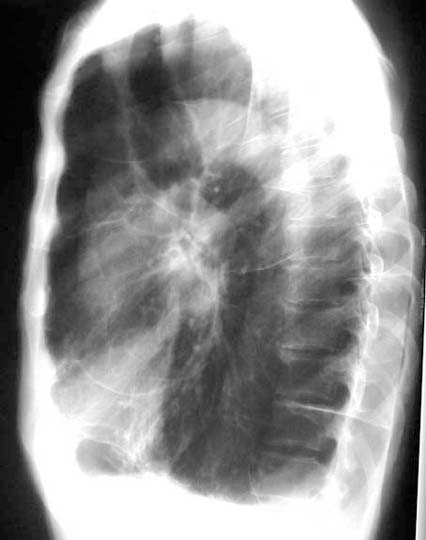

Case 23

Lateral

Upright

Lateral upright

Supine

Lateral decubitus

What are the common cavities where fungous ball forms?